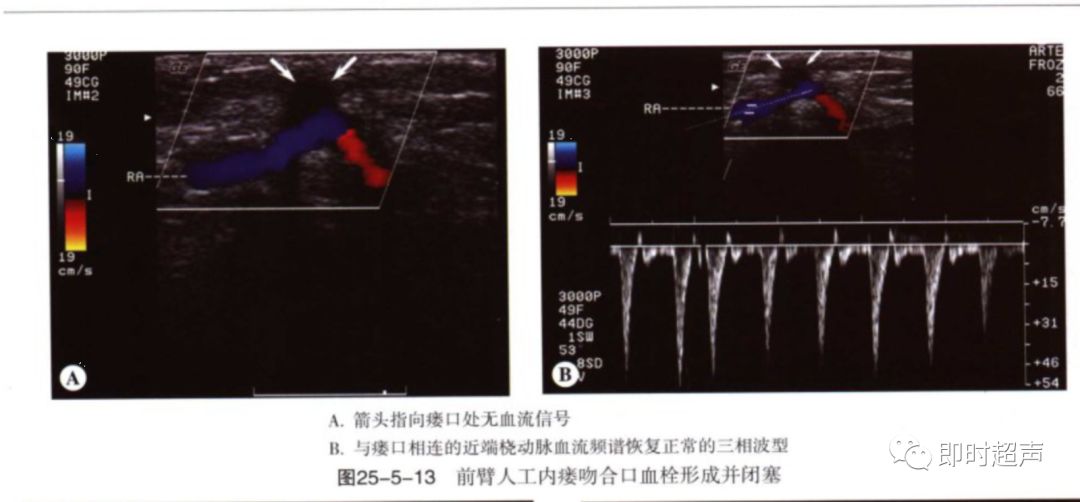

血栓:血栓与狭窄密切相关,常发于静脉侧,静脉管腔压瘪可除外血栓形成。闭塞处可见彩色多普勒血流中断,频谱多普勒信号消失。流入道动脉呈高阻频谱改变。

常见并发症-3